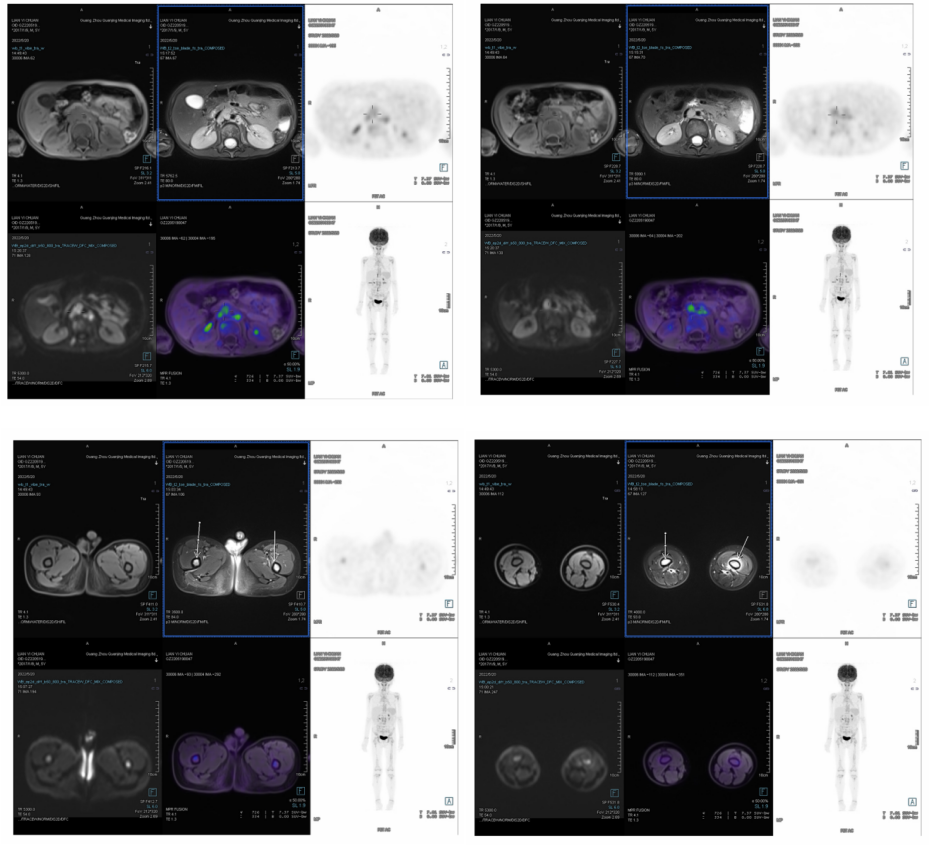

2022-5-9行PET/MRI检査示: 1.“神经母细胞瘤”综合治疗后:胸、腹主动脉旁及左锁骨上区多发结节,考虑淋巴结转移;全身多发骨转移及骨髓浸润,并左股骨干骨膜水肿;以上转移灶糖代谢活跃。2.甲状腺左叶下方结节,糖代谢轻度增高,考虑胸腺组织生理性摄取。3.双侧咽后间隙、颈部Ⅱ-Ⅴ区增大淋巴结,糖代谢增高,拟炎性增生,建议随诊。4.脾脏信号欠均,糖代谢轻度增高,考虑反应性改变。5.胸部CT示双肺未见异常。6.采集范围内其余部位未见异常糖代谢增高灶。

2022-5行PET/MRI提示多发淋巴结和骨转移